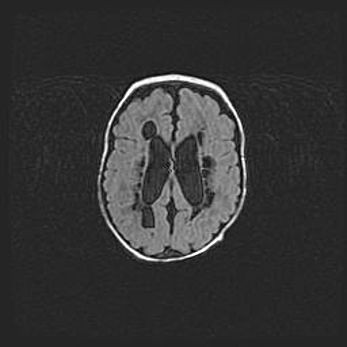

Множественные мелкие кисты перивентрикулярной области.

Киста прозрачной перегородки.

Возраст: 28 дней

Вес: 2400 г

Пол: женский

Окружность головы: 33 см

Срок гестации: 34 недели

Перивентрикулярная киста – это полостное образование в околожелудочковых областях белового вещества головного мозга. С морфологической точки зрения – это мелкоочаговая зона коагуляционного некроза, возникшая после инфаркта белого вещества. Наиболее часто поражаются начальные отделы задних рогов боковых желудочков. Обычно образования заполнены жидкостным содержимым.

Киста прозрачной перегородки может располагаться в переднем отделе межжелудочковой перегородки, в области мозолистого тела и мозжечка.